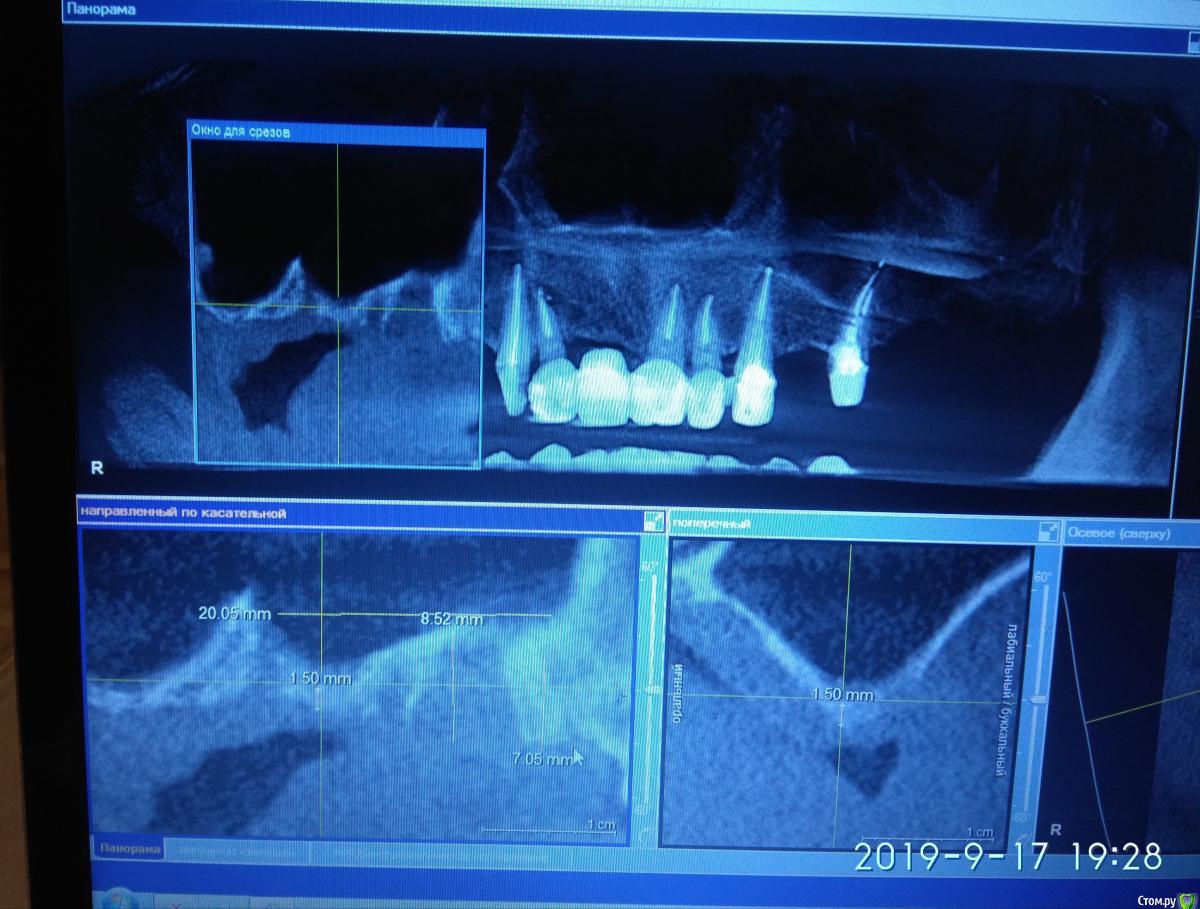

Irouil Опубликовано 30 сентября, 2019 Поделиться Опубликовано 30 сентября, 2019 (изменено) Покажите кт уже, может Вы по септе отслаиваетесь и рвете в одном месте постоянно Изменено 30 сентября, 2019 пользователем Irouil Ссылка на комментарий

rimtar Опубликовано 30 сентября, 2019 Автор Поделиться Опубликовано 30 сентября, 2019 Разрыв в области 15-14 примерно, по медиальному краю окна Ссылка на комментарий

Irouil Опубликовано 30 сентября, 2019 Поделиться Опубликовано 30 сентября, 2019 А где окно от первой попытки? Если дно везде такое плавное, то отслойка не должна вызывать проблем Ссылка на комментарий

rimtar Опубликовано 30 сентября, 2019 Автор Поделиться Опубликовано 30 сентября, 2019 это кт до первой попытки. по дну отслоился, разрыв в области верхне-медиального угла окна. по форме, размеру и расположению разрыв такой же, каким оставил предыдущий раз Ссылка на комментарий